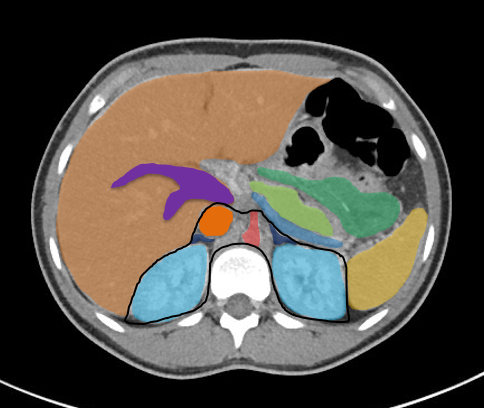

Bildergalerie (5 Bilder)